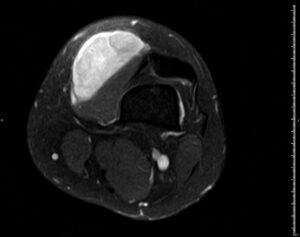

RM T1 con supresión grasa y contraste IV

HALLAZGOS RADIOLÓGICOS